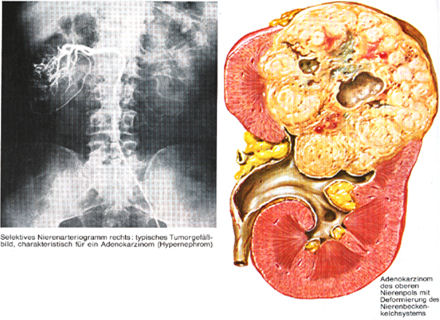

BİLGİSAYARLI TOMOGRAFİ (CT)

Hem böbrek pelvisi hem de üreterdeki kitleyi gösterebildiği gibi etraf dokulardaki metastazlarıda gösterebildiği için tercih edilmesi gereken bir tetkik yöntemidir.